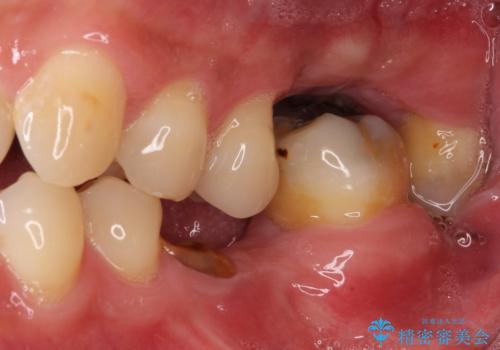

- 前歯や奥歯の虫歯を放置しており、それらの治療を契機に真っ白な歯にしたいとのことで来院された患者様です。

咬み合わせを改善するに当たって、抜歯しなければならない歯や歯列の改善が必要な箇所があったため、矯正治療やインプラント治療から始めていくこととしました。

不自然なくらい真っ白にしたいとのことでしたので、透明感のないフルジルコニアクラウンを用いて補綴することとしました。